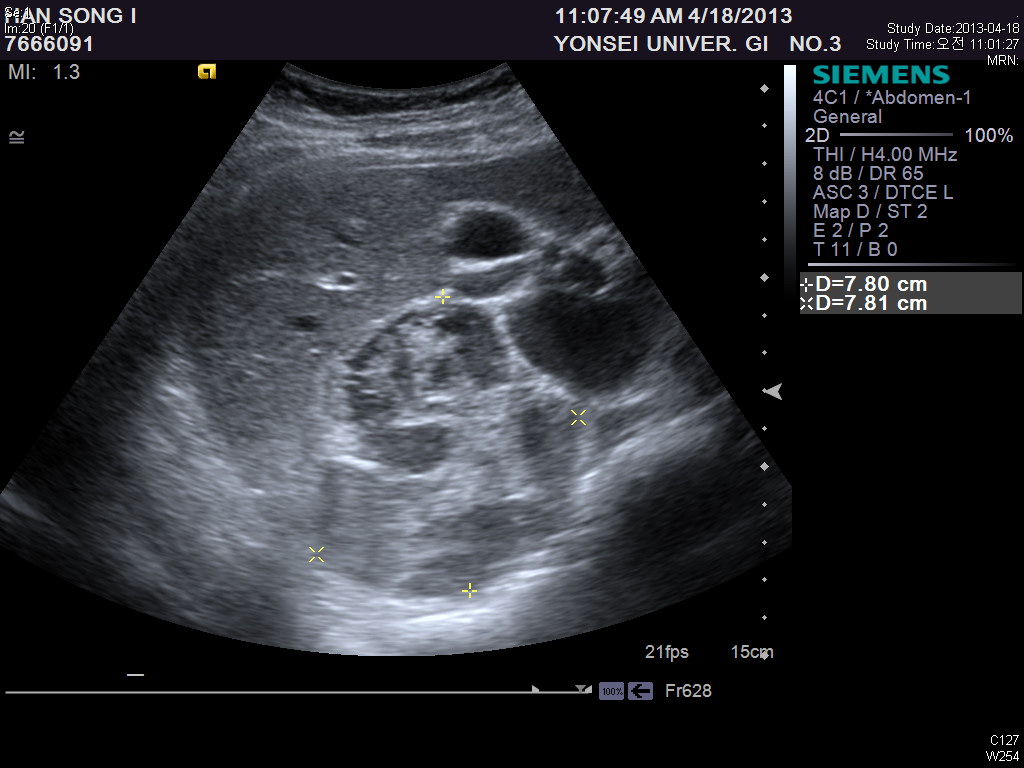

Context Adrenal cavernous hemangioma is a rare type of tumor that is usually diagnosed post-operatively. There have only been approximately 63 cases reported in the literature to date. Case report We report a case of adrenal cavernous hemangioma in a 27-year-old pregnant woman. The mass was discovered on ultrasonography when she visited a gastroenterologist for vague epigastric discomfort and vomiting. The laboratory tests were within normal limits and did not show any features suggestive of adrenal endocrinologic dysfunction. Computed Tomography (CT) revealed a well-defined 7.8 × 7.8 oval mass in the right adrenal gland with speckled calcifications. The mass was removed by transabdominal laparoscopic surgery. Strong positive immunostaining for CD31 and CD34 with weakly positive staining for podoplanin/D2-40 confirmed the diagnosis of cavernous hemangioma. Conclusions We reviewed 52 case reports of adrenal cavernous hemangioma in an attempt to identify tumor characteristics. More than half of the patients reviewed showed a heterogeneous internal structure of the mass with peripheral patchy enhancement on CT. They also showed focal or speckled calcifications either on X-ray or CT. Nevertheless, many of these characteristics overlap with the imaging phenotypes of other common diseases of the adrenal gland and therefore do not seem to provide definite evidence for differential diagnosis. Laparoscopic approach is a feasible and safe modality to remove adrenal cavernous hemangiomas because they seem to form a rigid fibrotic capsule; hence the risk of bleeding due to surgical manipulation is relatively low.